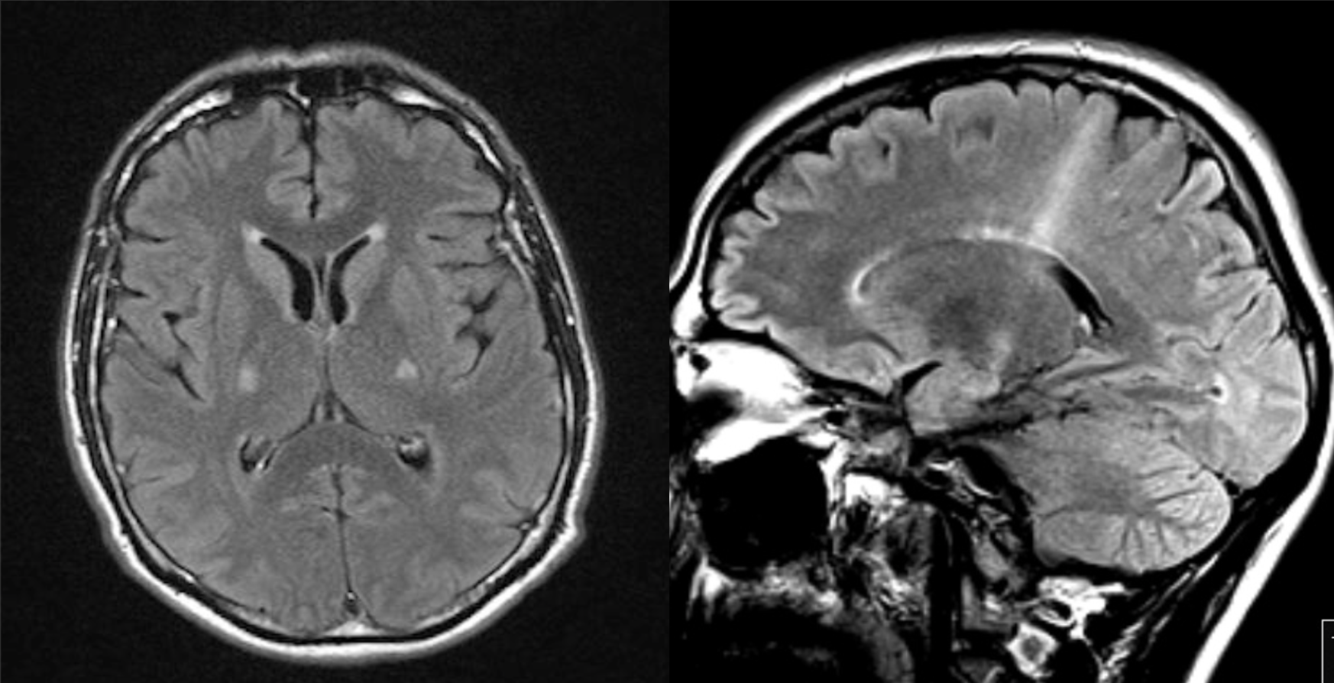

65 y/o alcoholic with confusion. The smaller, inset image is a normal MRI for comparison.

Wernicke’s encephalopathy